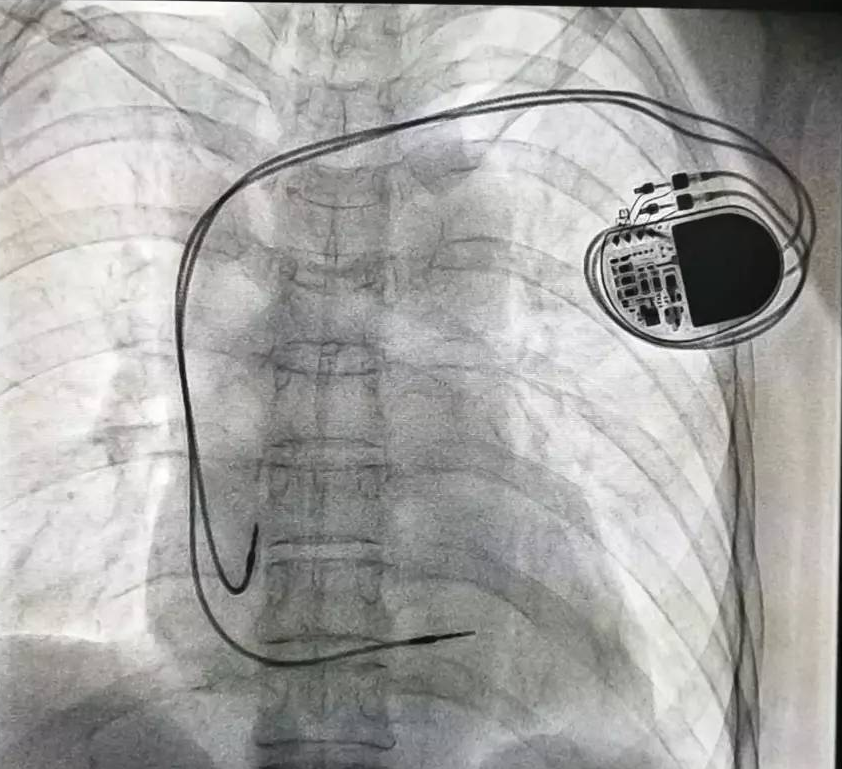

全球唯一!無線雙腔起搏器首次植入

來源:器械之家,未經(jīng)授權不得以任何形式轉(zhuǎn)載,且24小時后方可轉(zhuǎn)載。2022年2月7日雅培宣布,其在研型Aveir?雙腔無引線起搏器完成了全球首例患者植入,這也是全世界第一個雙腔無線起搏器。Aveir?DR雙腔起搏器提供右心房和心臟右心室的同步、逐次跳起搏,近80%接受起搏器治療的患者需要雙腔選擇,A